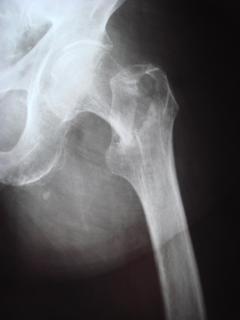

Τα εν λόγω κατάγματα είναι αρκετά συνηθισμένα και συχνά συμβαίνουν μετά από τροχαία ατυχήματα ή πτώση από ύψος. Παρατηρείται εξαιρετικά μεγάλη ποικιλία στη μορφή τους, κατα κανόνα όμως είναι σοβαρά και πολλές φορές ανοικτά – δηλ με τραύμα στο σημείο του κατάγματος – κάτι που αυξάνει τον κίνδυνο λοίμωξης και επιβαρύνει την πορεία της θεραπείας. Στα κατάγματα των άνω άκρων ενδέχεται να υπάρξει και τραυματισμός νεύρων, που χρειάζεται επίσης αντιμετώπιση.

Με τα σύγχρονα μέσα που διαθέτουμε, όλα σχεδόν αυτά τα κατάγματα πρέπει να αντιμετωπίζονται χειρουργικώς. Υπάρχει πληθώρα υλικών οστεοσύνθεσης (πλάκες διαφόρων τύπων, ενδομυελικοί ήλοι, συστήματα εξωτερικής οστεοσύνθεσης) που είναι διαθέσιμα και επαφίεται στην εμπειρία του χειρουργού η επιλογή.

Οπως και άλλοι εξοικειωμένοι χειρουργοί διεθνώς, χρησιμοποιώ τεχνικές ελάχιστης παρέμβασης (Minimal Invasive Surgery), δηλαδή μικρές τομές, επειδή έτσι το χειρουργικό τραύμα είναι ελάχιστο, με αποτέλεσμα ταχύτερη επούλωση. Ταχύτερη πώρωση των καταγμάτων, ταχύτερη κινητοποίηση.

Φυσικά το τελικό αποτέλεσμα θα εξαρτηθεί εν πολλοίς από τον τύπο του κατάγματος και την δεινότητα του χειρουργού.